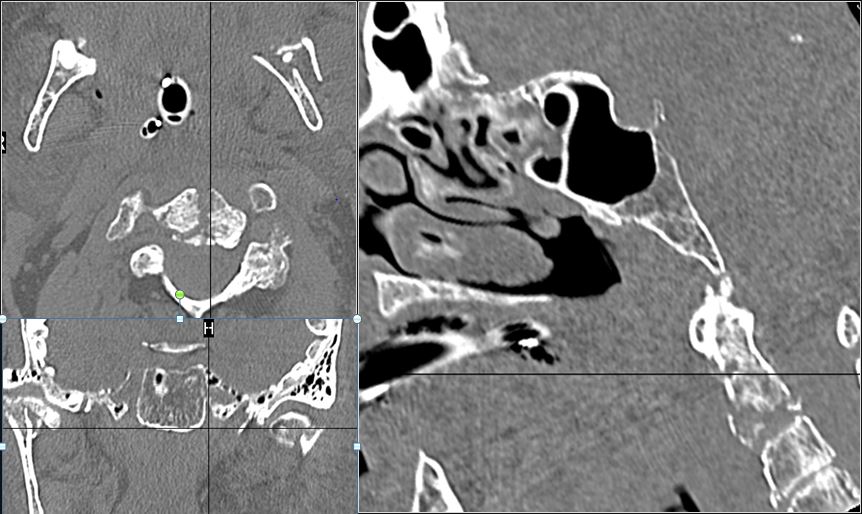

Mandible and Temporomandibular Joints

There is bony injury or displacement of the body, angle, ramus, parasymphyseal region, alveolar ridge, and condylar and coronoid process of the mandible. [In case of fracture, describe complexity and displacement]. [Yes/No]

The condylar head and fossa as well as the temporomandibular joint space are fractured and/or dislocated. [Yes/No]

There is condylar fracture either within or outside of the joint capsule, or with or without involvement of the articular surface of the condylar head. [Yes/No]

There is bony injury or displacement of the external auditory canal and/or other evidence of temporal bone injury. [Yes/No]